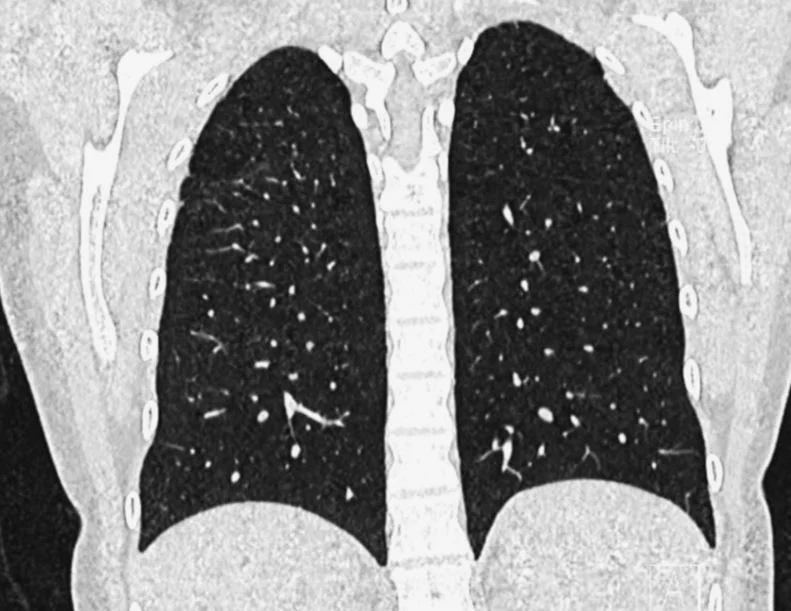

All the lung images are from a AATD patient

• Alpha-1 Antitrypsin Deficiency (AATD) is an inherited genetic disease of European origin characterized by an increased risk of illness in the lungs and liver, among other organs. Additionally, it is distinguished by a low percentage of the AAT protein that acts as an anti-inflammatory and protection source for the lungs. This protein is produced in the liver, and the liver of the patients does not release the protein due to low production levels. Consequently, as the protein accumulates, liver damage develops. People with AATD can suffer from chronic obstructive pulmonary emphysema (COPD), cirrhosis, and other medical issues.

To date, there is no known cure for the disease, but there are treatments that help reduce lung damage, such as respiratory therapy, lung and liver transplantation, and augmentation therapy. Patients take this treatment throughout their lives which consists of receiving a weekly dose of AAT protein intravenously to help the lungs. However, there is currently no treatment for liver damage.